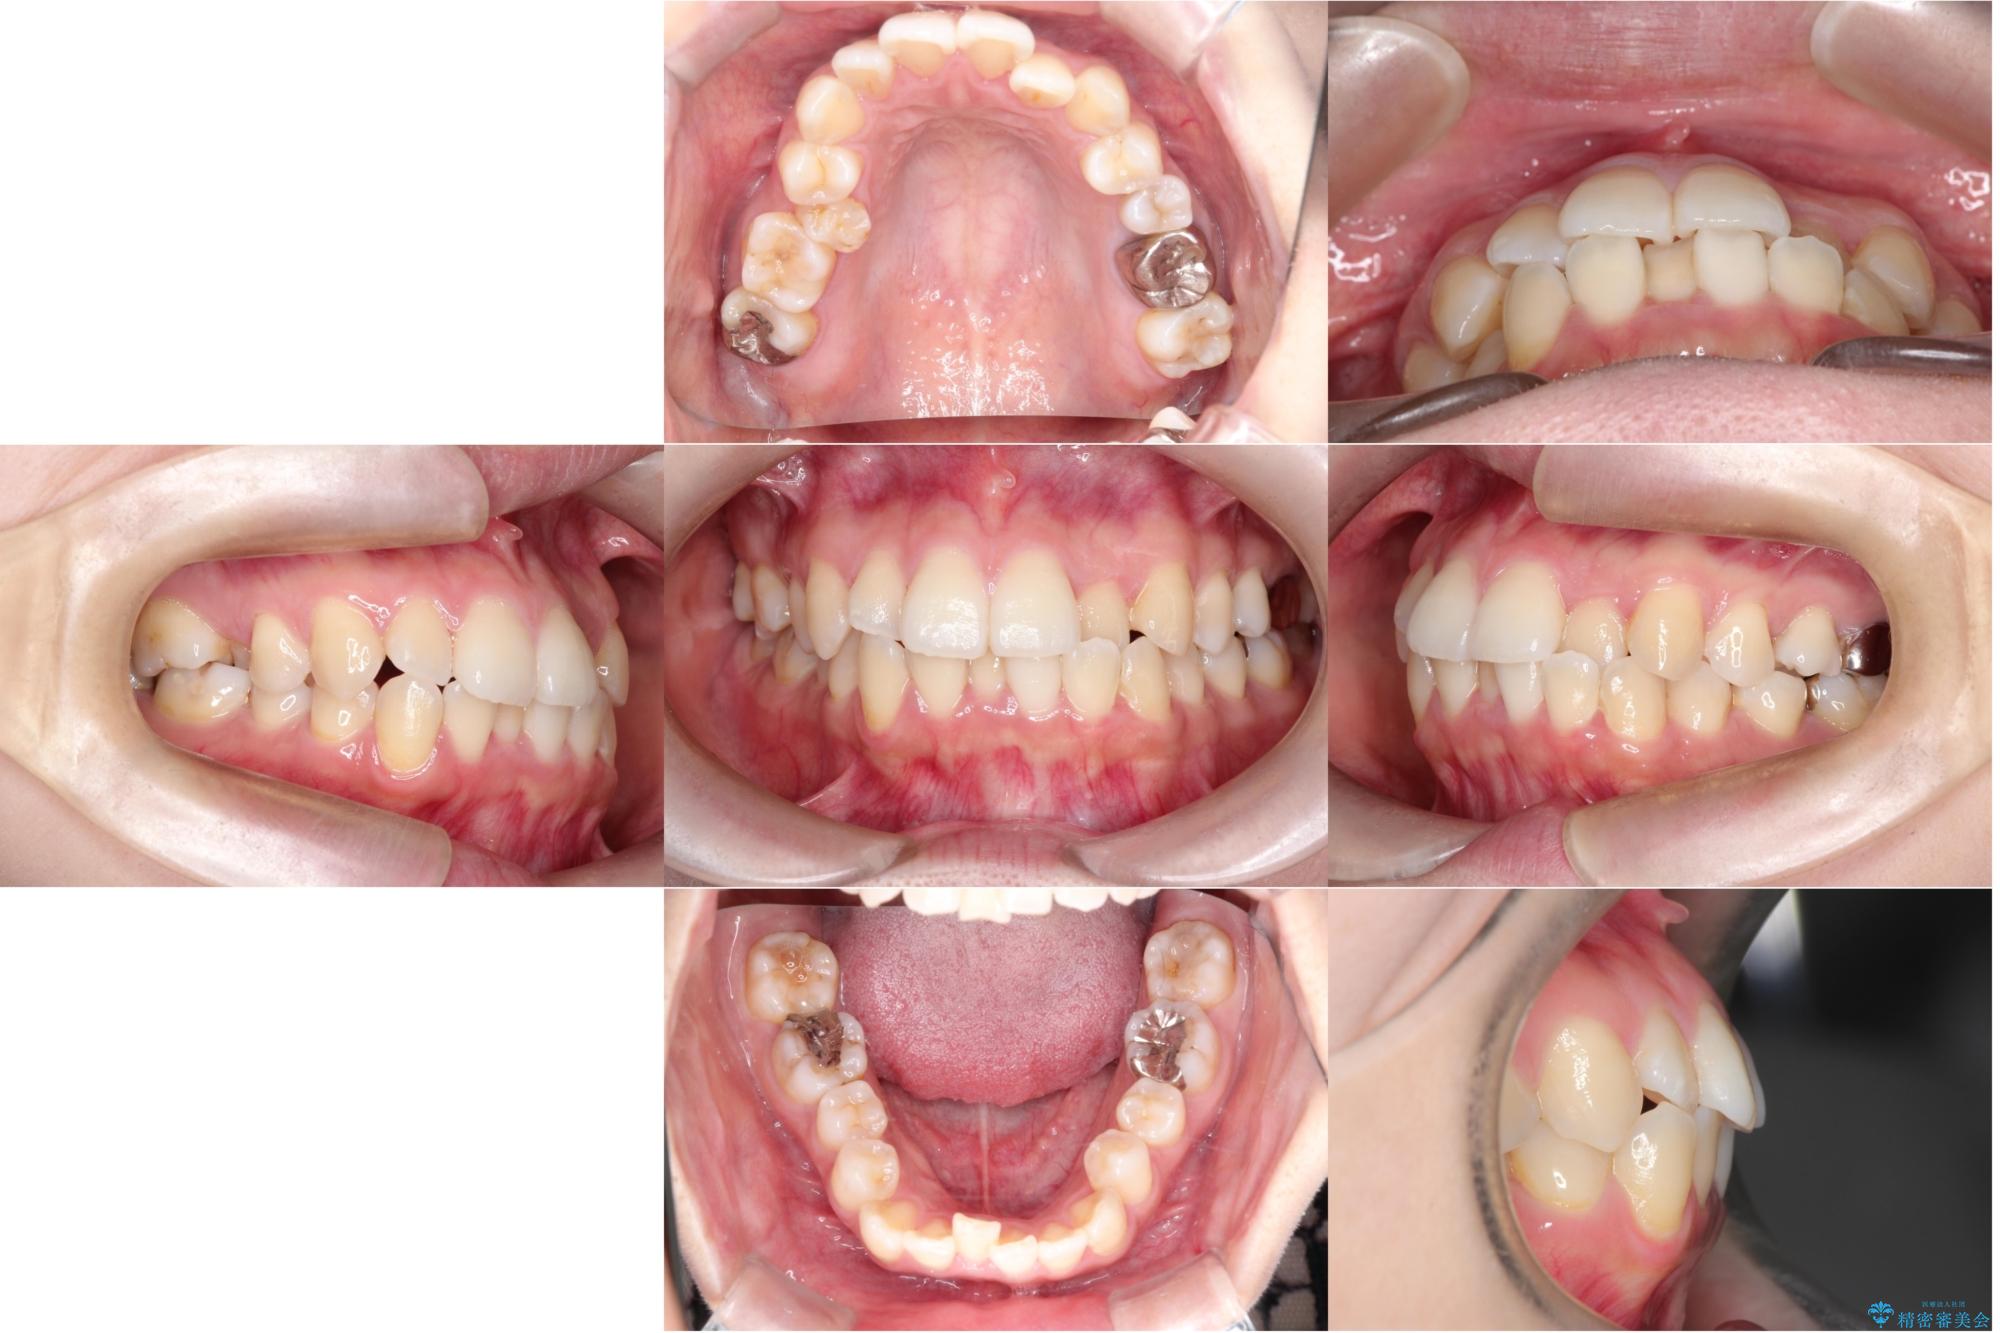

- 主訴:口元を下げて前突感を無くしたい、下の歯の凹凸も無くしたい

右側第二小臼歯、左側第一小臼歯、下顎両側第一大臼歯を抜歯しワイヤ-矯正を行いました。

骨格的顎の変位を認めたため、顔貌に対しピッタリ上下の歯の正中を合わせることは難しいと説明し、上下左右計4本小臼歯を抜歯しワイヤー矯正治療を行いました。